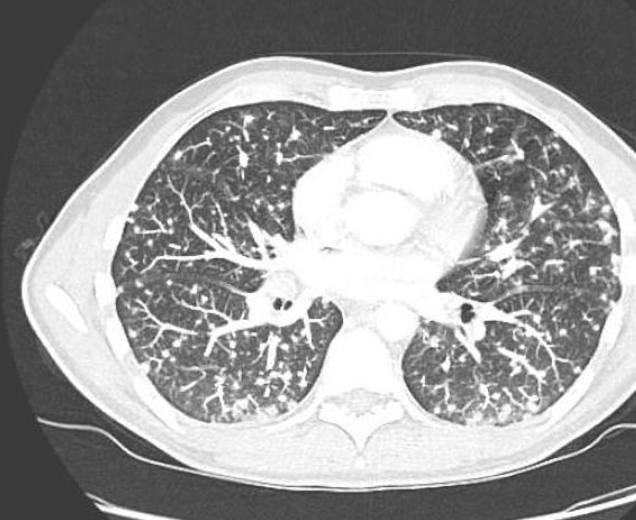

ACUTE INTERSTITAL PNEUMONIA

• Appears similar to ARDS but often with a symmetric Lower Lobe distribution

• EXUDATIVE PHASE (shown in pic one case)

• GGO

• Consolidation

• ORGANISING PHASE (pic two)

• architectural distortion

• traction bronchiectasis

• Honey combing